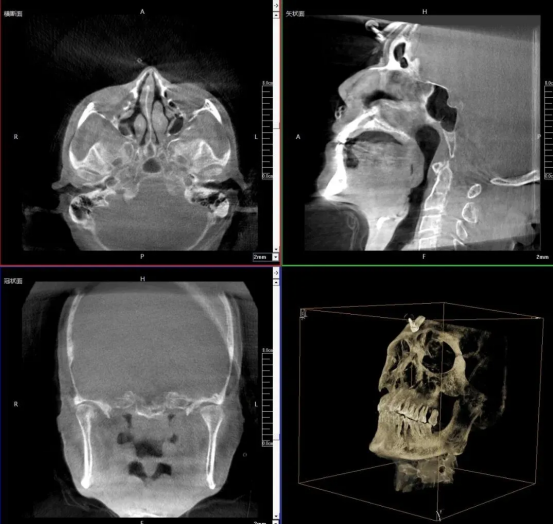

3D Image-Guided Localization of the Foramen Ovale

The patient is placed in a supine position. The C-arm is flexibly adjusted to the optimal scanning angle to perform rapid 3D scanning of the foramen ovale region at the skull base. The device automatically reconstructs a 3D anatomical model of the foramen ovale and the surrounding skull, clearly displaying the spatial location, aperture size of the foramen ovale as well as its adjacency to surrounding structures, thereby providing an accurate anatomical basis for puncture path planning.

Based on the 3D images, the doctor plans the optimal puncture path to ensure precise alignment between the puncture direction and the foramen ovale, minimizing puncture deviations.

With rapid 3D scanning and reconstruction technology, the device can clearly visualize the 3D spatial structure of the foramen ovale and trigeminal nerve. It addresses the problem that traditional 2D fluoroscopy struggles to accurately assess depth and critical spatial relationships with adjacent anatomy, thus providing reliable support for puncture path planning in complex clinical cases.